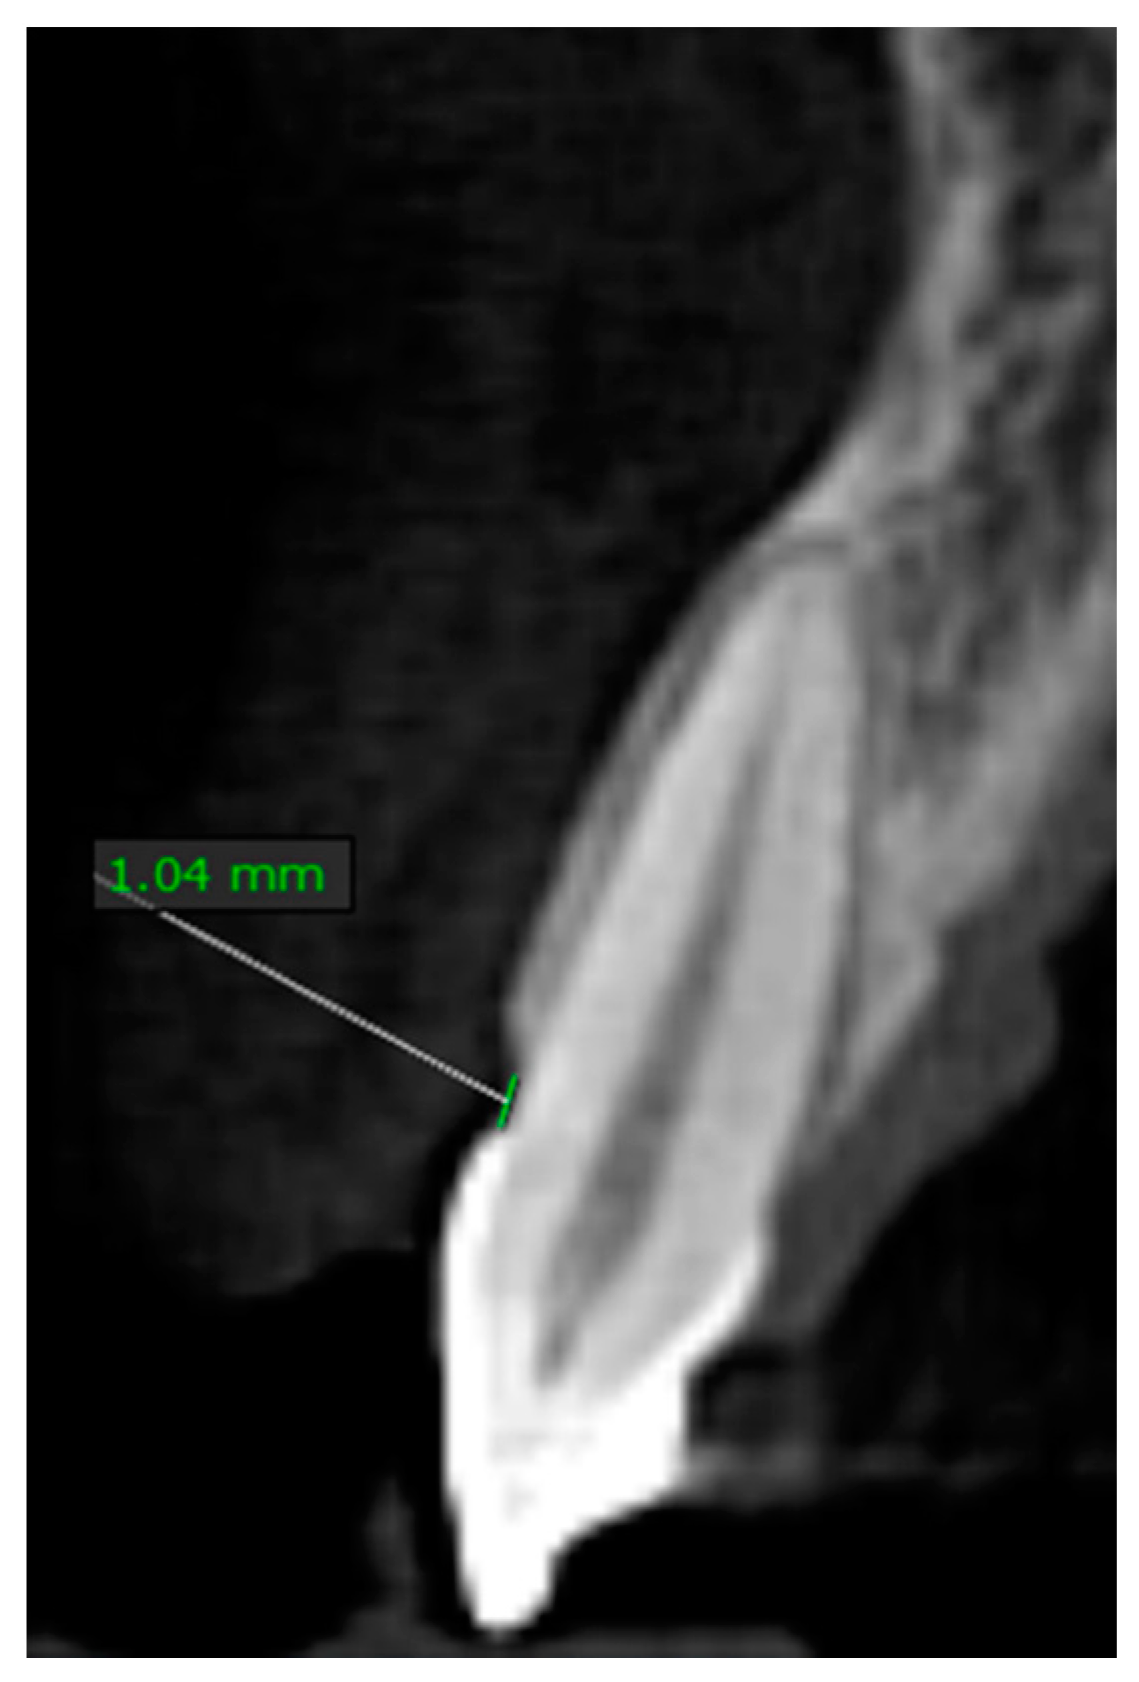

Furthermore, there were no significant findings on the extra-oral examination and patient was normally asymmetrical. The facial three thirds were analyzed and found to be normal. A lateral cephalometric analysis confirmed absence of vertical maxillary excess and dentoalveolar extrusion. The maxillary lip length was 19 mm, the incisal display at rest was 4 mm, and the lip mobility was also assessed and found to be 6 mm. The clinical crown lengths of central incisors, lateral incisors, and canines teeth were 8 mm, 7 mm, and 8 mm, respectively. The gingival phenotype was assessed using the probe-transparency test4 and was determined to be thick. A CBCT scan (CS9300; Carestream Health Inc., Kodak, Rochester, NY, USA) was acquired to analyze the level of the alveolar bone crest in relation to the cementoenamel junction. The radiographic parameter was set as 90 kVp/4 mA/s, with voxel size 200 μm, according to manufacturer’s exposure settings with a field of view 10 × 5 cm (diameter × height). Based on the sagittal cross section of the maxillary anterior sextant, the distance between the bone crest and the respective cementoenamel junction was at a maximum of 1.5 mm (Figure 2). The CBCT scan also showed that the patient had a thick buccal cortex. Due to the short clinical crowns presentation, the squarish appearance of the teeth, and the aforementioned clinical findings, the patient was diagnosed with excessive gingival display as a result of altered passive eruption APE type 1 with a low bone crest. Treatment options were discussed with the patient and esthetic crown lengthening with bone resection was proposed.

Figure 2.

Distance from cementoenamel junction to facial bone crest as measured on cone beam computed tomography (CBCT).